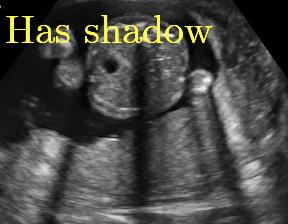

Sound-opaque occluders, including bones and calcified tissues, block the propagation of sound waves by strongly absorbing or reflecting sound waves during scanning. The regions behind these sound-opaque occluders return little to no reflections to the US transducer. Thus these areas have low intensity but very high acoustic impedance gradients at their boundaries (e.g. Fig. 1(a) left column). Reducing acoustic shadows and correct interpretation of images containing shadows rely heavily on sonographer experience. Experienced sonographers avoid shadows by moving the probe to a more preferable viewing direction during scanning or, if no shadow-free viewing direction can be found, a mental map is compounded with iterative acquisitions from different orientations.

We propose a novel method based on convolutional neural networks (CNNs) to automatically estimate pixel-wise confidence maps of acoustic shadows in 2D US images. Our method learns an initial latent space of shadow regions from images consisting of multiple anatomies and with global image-level labels (“has shadow” and “shadow-free”), e.g. Fig. 1(a). The basic latent space is then estimated by learning from fewer images of a single anatomy (fetal brain) with coarse pixel-wise shadow annotations (approximately of the images with global image-level labels), e.g. Fig. 1(b). The resulting latent space is then refined by learning shadow intensity distributions using fetal brain images so that the latent space is suitable for confidence estimation of shadow regions. By using shadow intensity information, our method can detect more shadow regions than the coarse manual segmentation, especially relatively weak shadow regions.

We propose a shadow-seg module to extract generalized shadow features for a large range of shadow types in fetal US images under limited weak manual annotations. Since shadow regions have different shapes, various intensity distributions and uncertain edges, the pixel-wise annotation of shadow regions is time consuming and relies heavily on annotator’s experience (e.g. various annotations in Fig. 1(b)). This generally results in manual annotations of limited quantity and quality. Compared with pixel-wise shadow annotations, global image-level labels (“has shadow” and “shadow-free” in our case) are easier to obtain, and shadow images with global image-level labels can contain a larger variety of shadow types. Therefore, we use a shadow-seg module that combines unreliable pixel-wise annotations and global image-level labels as weak annotations.The proposed shadow-seg module contains two tasks, (1) shadow/shadow-free classification using image-level labels, and (2) shadow segmentation that uses few coarse pixel-wise manual annotations ( of the global image-level labels). Shadow features can be extracted during simple shadow/shadow-free classification and subsequently optimized for the more challenging shadow segmentation task. In our case, shadow features extracted by the classification network cover various shadow types in a range of anatomical structures. These shadow features become suitable for the shadow segmentation after being optimized by a shadow segmentation network.